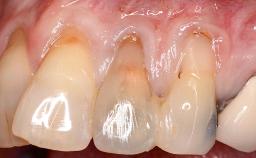

It is sometimes necessary to remove and replace compromised implants. This case is a clear example of the need for multiple steps to achieve an optimal therapeutic result for patients with non-salvageable implants. It illustrates how the lost soft and hard tissues were rebuilt in a sequence that improved the healing of the hard tissues and assured their long-term stability. The 35-year-old healthy patient presented with clinical attachment loss on the proximal and lingual surfaces of the natural dentition. Some gingival recession was present on natural teeth, particularly in the posterior sextants (S1, S3, S4, and S6).

Soft Tissue Anatomy Intact Defective

Bone Volume Horizontally and vertically sufficient Horizontally deficient Deficient vertically or deficient vertically AND horizontally